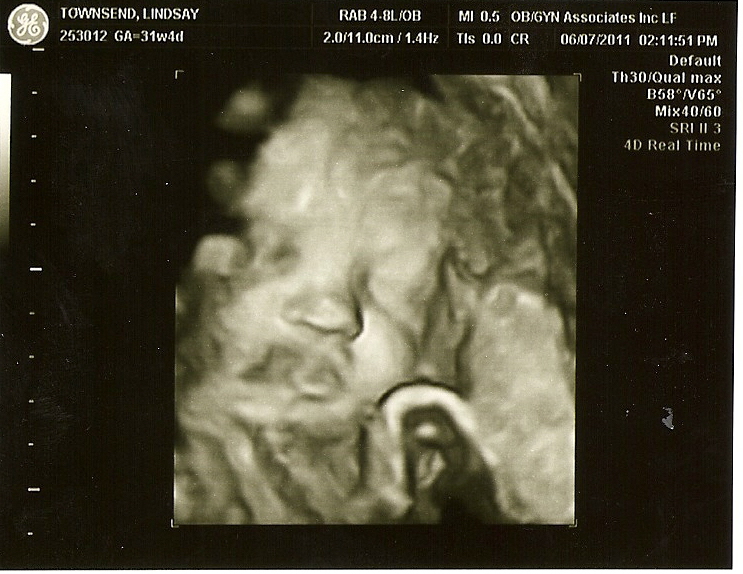

Cameron's cute little face, his lips look funny, b/c the umbilical cord is running acrossed them, but his lips are normal. Who's nose do you think he has?

Today I had another ultrasound to follow-up on why my belly was measuring small last week and to follow-up on my bloodwork. The ultrasound showed that he is weighing 3 pounds 11 ounces, his head was measuring in the 90th Percentile, which I believe I saw was about 8cm. His belly only measured in the 3rd Percentile, which is a little small for where he is supposed to be. I think when she was measuring his belly is gestational age was 29 weeks for his belly. His overall age, was 32 weeks 4 days. The ultrasound tech said that his head was making up for his belly at this point. He is also head down already at this point and I believe he was facing my right side and that his feet are up and around my right side which is where he has been jabbing me in the side pretty good. We got to see all 4 chambers of his heart funtioning good, he was also breathing, but he was being difficult he would breath several times and stop and then breath again. The ultrasound tech said that was all normal though. My cervix, placenta, and amniotic fluid all looked good along with the blood flow threw the umbilical cord. The babies heart rate was 151 bpm. Overall, everything looked good besides his belly measurement. All of my bloodwork, blood pressure, and weight all looked good. Due to his belly measurement the doctor recommended that I get a weekly BioPhysical Ultrasound which measures his fetal movements and follow-up with the doctor following the ultrasound, and then in 3 weeks we will get another growth ultrasound to make sure he is continuing to grow like he is supposed to. She just instructed me to count his kicks and make sure I am counting 10 kicks in an hour just once a day. So all in all everything looked good. Let just keep our fingers crossed that everything continues to look good and we have a healthy little boy in about 8 1/2 weeks.